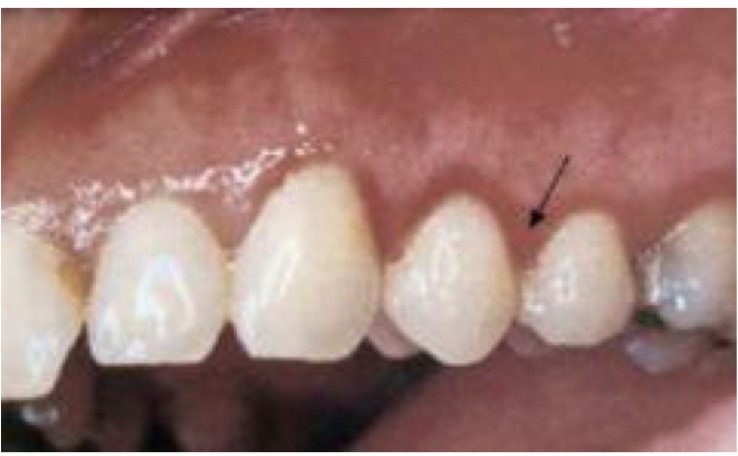

KHÔ MIỆNG ( nếu ls có nhắc sau xạ trị—> KHÔ MIỆNG SAU XẠ TRỊ)

CHẨN ĐOÁN?